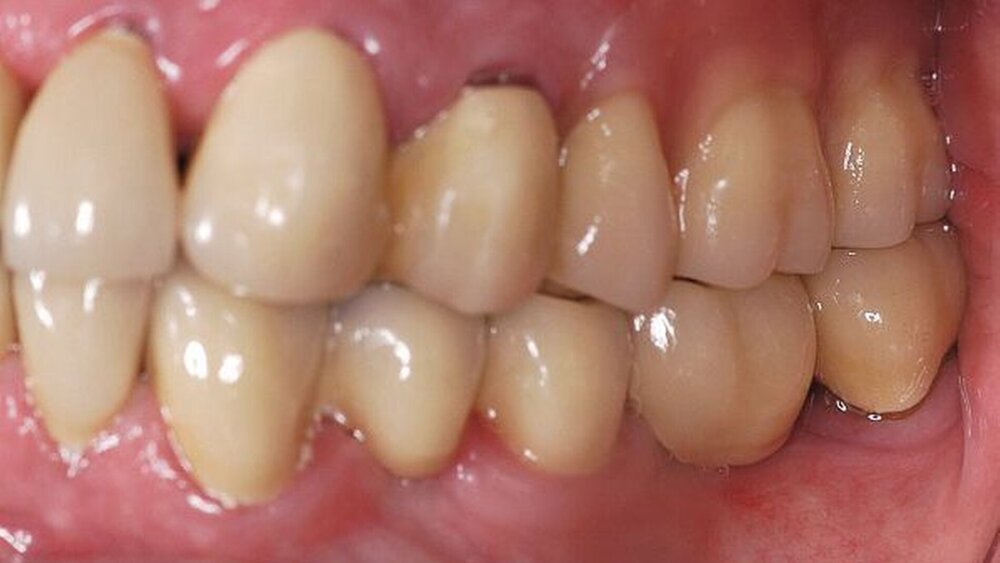

In der darauf folgenden Sitzung wurden alle Kronen und Brücken sowie die teleskopgetragene, partielle obere Prothese für einen Zeitraum von sieben Tagen zum Probetragen mittels eines Zements auf Zinkoxid-Eugenol-Basis eingegliedert. Dem Patienten sollte durch das Probetragen der Restaurationen beziehungsweise des angefertigten Zahnersatzes die Möglichkeit gegeben werden, sowohl die Funktion beim Essen und Sprechen als auch die Ästhetik im sozialen Umfeld zu testen. Ein erneutes Entnehmen der Restaurationen wäre – für den Fall notwendiger Korrekturen – somit ohne Weiteres möglich gewesen. Da der Patient sowohl die Funktion als auch die Ästhetik betreffend keine Änderungswünsche vorbrachte und auch keine neuerlichen Beschwerden aufgetreten waren, konnten die Restaurationen nach besagtem Tragezeitraum von sieben Tagen entnommen, gesäubert und mittels eines Glasionomerzements definitiv befestigt werden. Im Anschluss wurden erneut Situationsabformungen der Kiefer genommen und der Patient erhielt nach erneutem Checkbiss-Registrat, eine okklusal adjustierte Stabilisierungsschiene im Unterkiefer. Diese dient der Therapie der beschriebenen Bruxismusproblematik und gewährleistet einen langfristen Erfolg der eingegliederten prothetischen Restaurationen (Abbildungen 13a, 13b, 13c, 14, 15a, 15b, 15c).

Abschließend kann somit festgehalten werden, dass durch die gewählte Restaurationsform sowie durch die Art der technischen Umsetzung ein funktionell und ästhetisch sehr gutes Ergebnis erreicht werden konnte. Die Prognose des angefertigten Zahnersatzes ist bei entsprechender Compliance des Patienten sowie aufgrund der guten werkstofftechnischen Eigenschaften über einen Zeitraum von vielen Jahren als sehr gut einzustufen (Abbildungen 16a, 16b, 16c, 16d, 16e ).